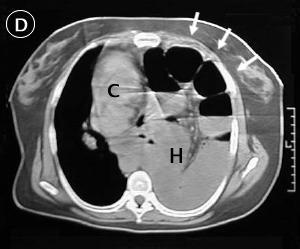

Corte Tomográfico D

Flechas: La brecha diafragmática.

c: corazón desplazado a la derecha.

H: El hemitorax izquierdo ocupado por las asas intestinales, ausencia de parenquima pulmonar